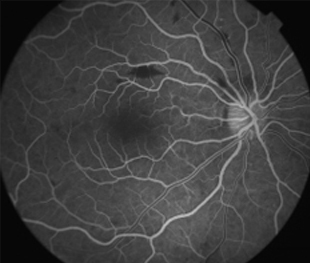

Angiografía OI

- Angiografía: teñido arterial, escape capilar, más tardíamente, no perfusion arteriolar y venular con teñido de las paredes vasculares y dilatación venosa.